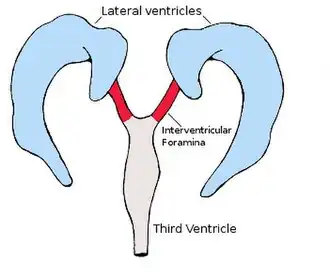

The lateral ventricles are the two largest ventricles of the brain and contain cerebrospinal fluid.[1] Each cerebral hemisphere contains a lateral ventricle, known as the left or right lateral ventricle, respectively.

Each lateral ventricle resembles a C-shaped cavity that begins at an inferior horn in the temporal lobe, travels through a body in the parietal lobe and frontal lobe, and ultimately terminates at the interventricular foramina where each lateral ventricle connects to the single, central third ventricle. Along the path, a posterior horn extends backward into the occipital lobe, and an anterior horn extends farther into the frontal lobe.[1]

Between the inferior horn and the main body of the ventricle is the putamen, which emerges from the head of the caudate nucleus, and sits above the tapetum; a small number of further connections passing through the occipital tapetum to join the putamen to portions of the caudate nucleus tail adjoining the anterior horn. Below the putamen sits the globus pallidus, with which it connects. These structures bounding the lateral ventricles form a frame curving around the thalamus, which itself constitutes the main structure bounding the third ventricle. Were it not for the choroid plexus, a cleft-like opening would be all that lay between the lateral ventricle and the thalamus; this cleft constitutes the lower part of the choroid fissure. The thalamus primarily communicates with the structures bounding the lateral ventricles via the globus pallidus, and the anterior extremities of the fornix (the mamillary bodies).[1]

During the first three months of prenatal development, the central canal expands into lateral, third, and fourth ventricles, connected by thinner channels.[6] In the lateral ventricles, specialized areas – choroid plexuses – appear, which produce cerebrospinal fluid. The neural canal that does not expand and remains the same at the level of the midbrain superior to the fourth ventricle forms the cerebral aqueduct. The fourth ventricle narrows at the obex (in the caudal medulla), to become the central canal of the spinal cord.